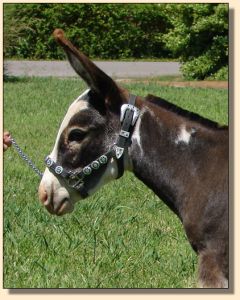

Height June 24th, 2008: 27¼"

Pony-Tailed Lass Update

- 11/09/07 @ 10:34am: PTL is out of surgery!! She is up and nursing. She will stay at UTK

until Tuesday for observation and is expected to be able to come home on Tuesday! The vet

that did the surgery is Dr. Blackford. The retired vet that is an expert in this kind of

surgery that advised Dr Blackford about the surgery was Dr. Krahwinkle.

11/19/07: Pony-Tail is home from her

operation and so far it is a complete success!

Update 12/09/07: Pony-Tail is continuing

to do well. She is going for her check up next week when we schedule her visit back to the

vet school in Knoxville. You can see her on our barn cam occasionally as she has free access

to all four cams now.

12/12/07: Pony-Tail's check-up at the University of Tennessee

Vet School today was a good one.

1/02/08: Pony-Tail's final checkup at the University

of Tennessee Vet School was today and she received a clean bill of health and was pronounced

well. She does not have to go back to the vets unless complications arise later down the

road!

9/24/08: Today is PTL's 1st birthday! We are having a party! Join us in person